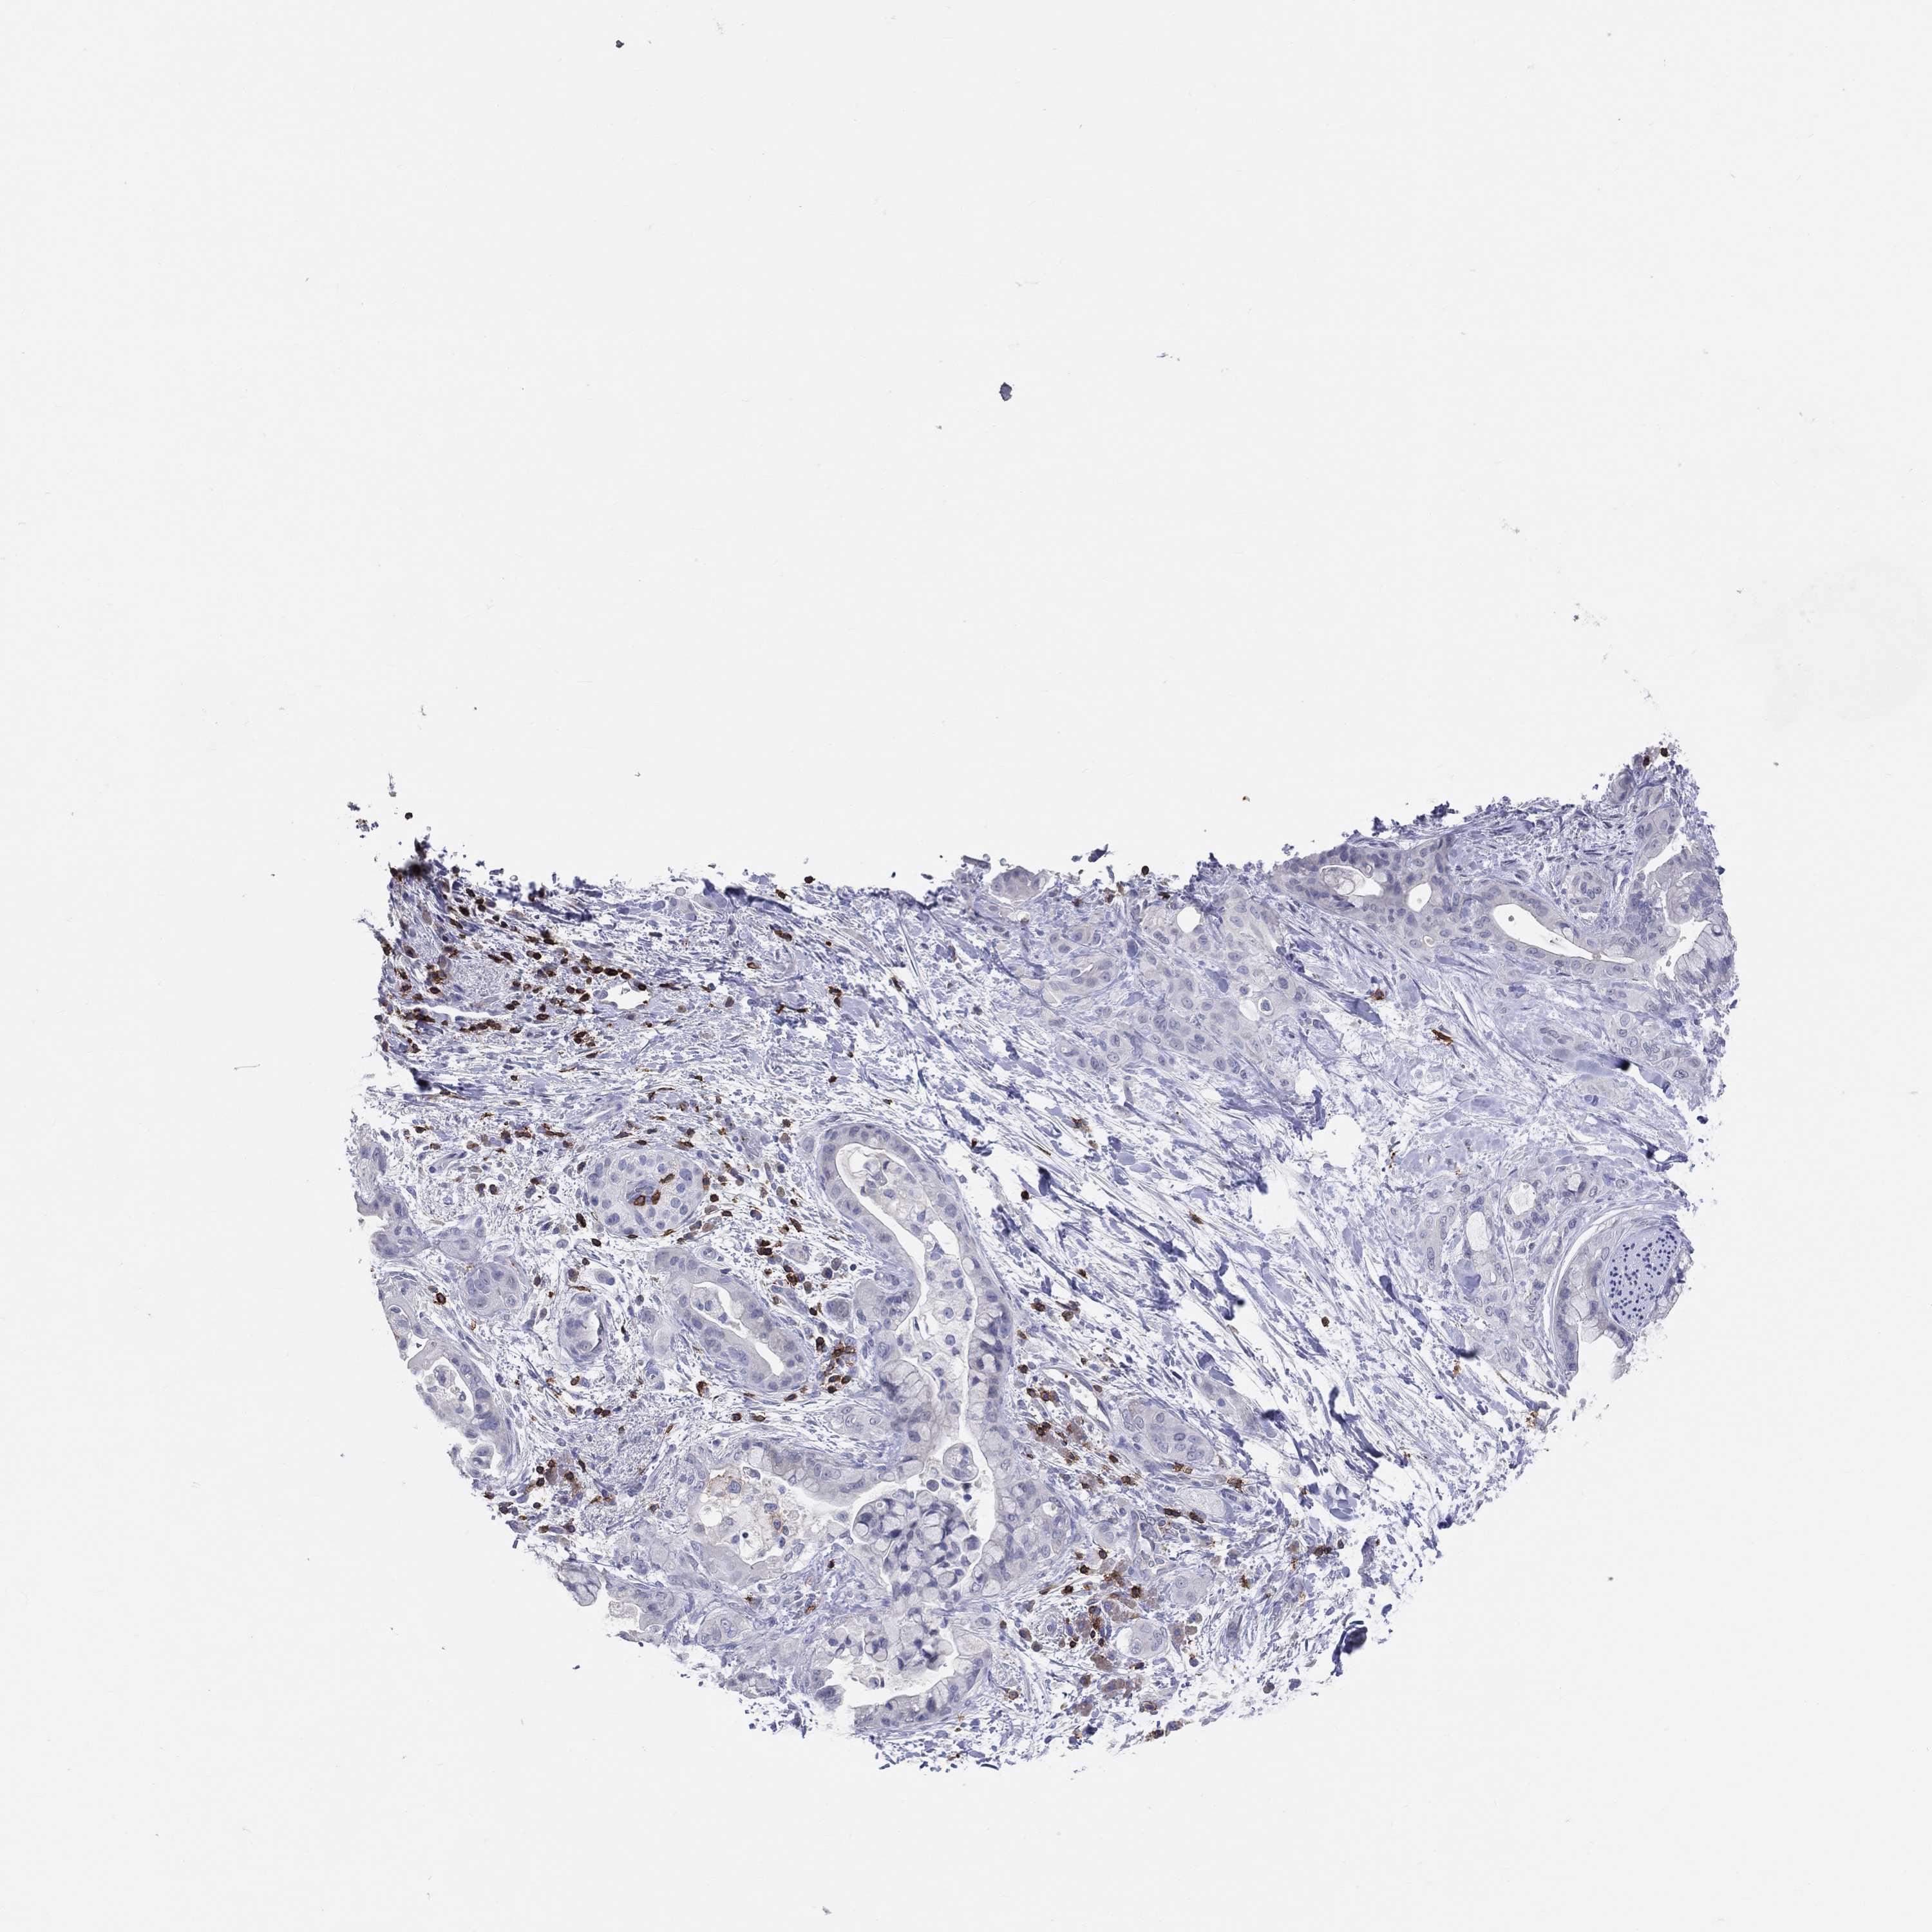

PANCREATIC CANCER - Protein expressioni

A mouse-over function shows sample information and annotation data. Click on an image to view it in a full screen mode. Samples can be filtered based on level of antibody staining by selecting one or several of the following categories: high, medium, low and not detected. The assay and annotation is described here.

Note that samples used for immunohistochemistry by the Human Protein Atlas do not correspond to samples in the TCGA dataset.

Antibody stainingi

Antibody staining in the annotated cell types in the current human tissue is reported as not detected, low, medium, or high, based on conventional immunohistochemistry profiling in selected tissues. This score is based on the combination of the staining intensity and fraction of stained cells.

Each image is clickable and will lead to virtual microscopy that enables deeper exploration of all samples and also displays staining intensity scores, fraction scores and subcellular localization as well as patient and tissue information for each sample.

Antibody HPA011157

Antibody CAB002223

Antibody CAB012978

Antibody CAB079960

Adenocarcinoma, NOS

Adenocarcinoma, metastatic, NOS